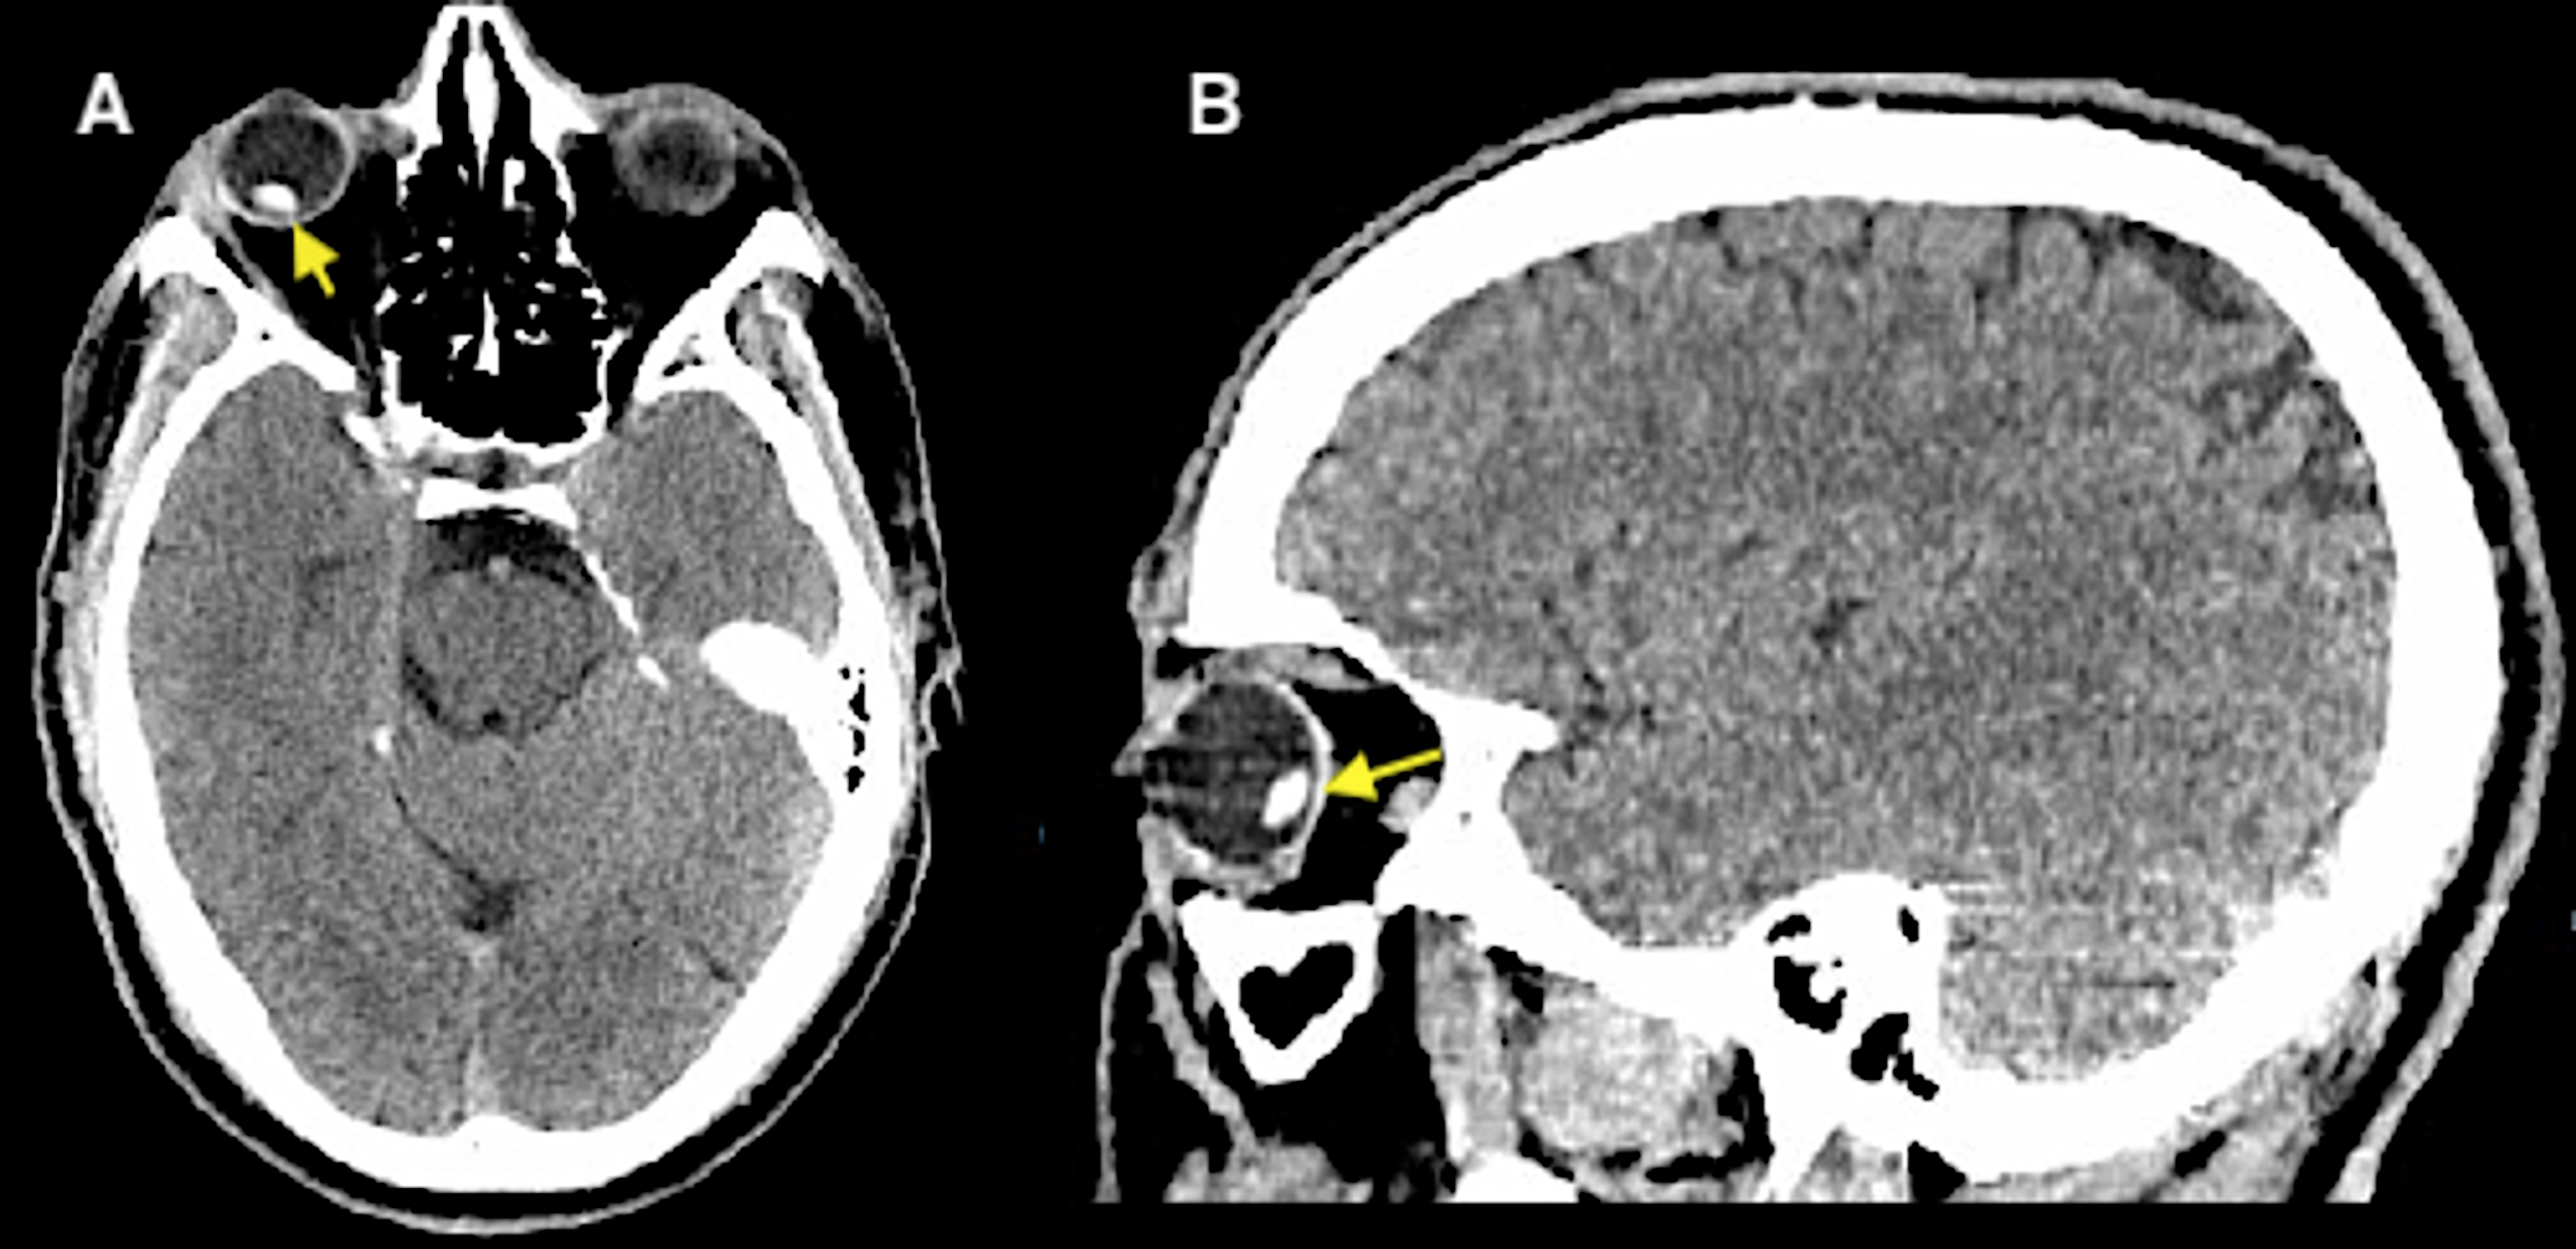

From www.researchgate.net

Posttraumatic lens dislocation. Download Scientific Diagram Eye Lens Dislocation Symptoms The degree to which vision is affected will depend on the severity of the dislocation. A dislocated lens often causes blurred vision. Ectopia lentis happens when the lens in your eye is dislocated or moved out of its normal place. Dislocation of your intraocular lens can cause vision problems and even blindness. The most common symptom of a dislocated iol. Eye Lens Dislocation Symptoms.